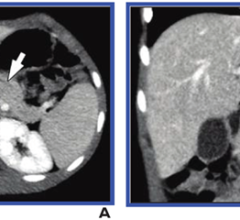

October 30, 2023 — According to the American Journal of Roentgenology (AJR), the conventional skeletal muscle area (SMA) ...